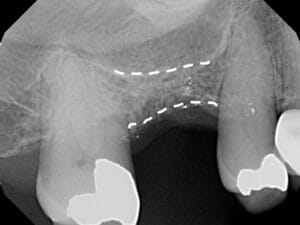

Ridge Preservation

Once a tooth is removed the bone shrinks to help the body efficiently use its resources. It is important to preserve the bone ridge before this happens. The most effective time for this is during a tooth extraction. During this procedure, the body normally forms a blood clot in a large empty space. After the wound contracts during healing, the bony ridge has become much smaller, possibly too small for an implant. When we perform grafting, wound contraction is prevented, leaving the bone ridge in its original shape and ready for an implant. If you'd like to learn more about bone grafting for dental implants, Jacksonville & surrounding areas contact us today at one of our four convenient locations.